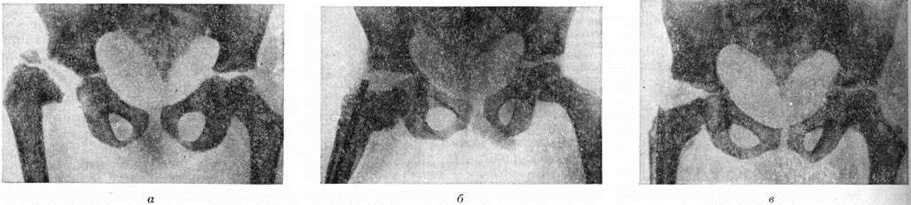

Гнойный Остеоартрит рентгенологически диагностируют только в разгар болезни, на 2—3-й неделе от начала заболевания,— обнаруживают разрушение участка метафиза кости, полное или частичное исчезновение ядра окостенения эпифиза, нарушение нормальных взаимоотношений костей в суставе, утолщение мягких тканей сустава. При этом ранняя диагностика этого тяжёлого поражения (рисунок 2) должна базироваться на соответствующей клинические, картине и данных лабораторный исследований.

Рис. 3. | ||

Длительно и злокачественно протекающий ревматоидный артрит также может привести к Остеоартрит, когда воспалительный процесс с синовиальной оболочки, капсулы сустава, связок переходит на эпифизы, что проявляется образованием краевой деструктивной их узурации (рисунок 3). В отличие от гнойных Остеоартрит костные сращения в поражённых ревматоидным артритом суставах наблюдаются редко, но в суставах запястья все же могут развиваться.